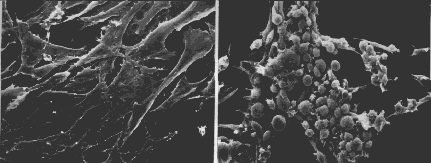

Cancer cells show no contact inhibition. Once the surface of the dish is covered, the cells continue to divide, piling up into mounds.

The photographs (courtesy of G. Steven Martin) show mouse fibroblasts (connective tissue cells) growing in culture. The cells on the left show contact inhibition. Those on the right do not. The cells on the right are said to be transformed. These cells (called 3T3 cells) were not derived from a mouse cancer but were produced by laboratory treatment of normal cells. Radiation, certain chemicals, and certain viruses are capable of transforming cells. Although transformed cells are not derived from cancers, they can often develop into malignant tumors when injected into an appropriate test animal.